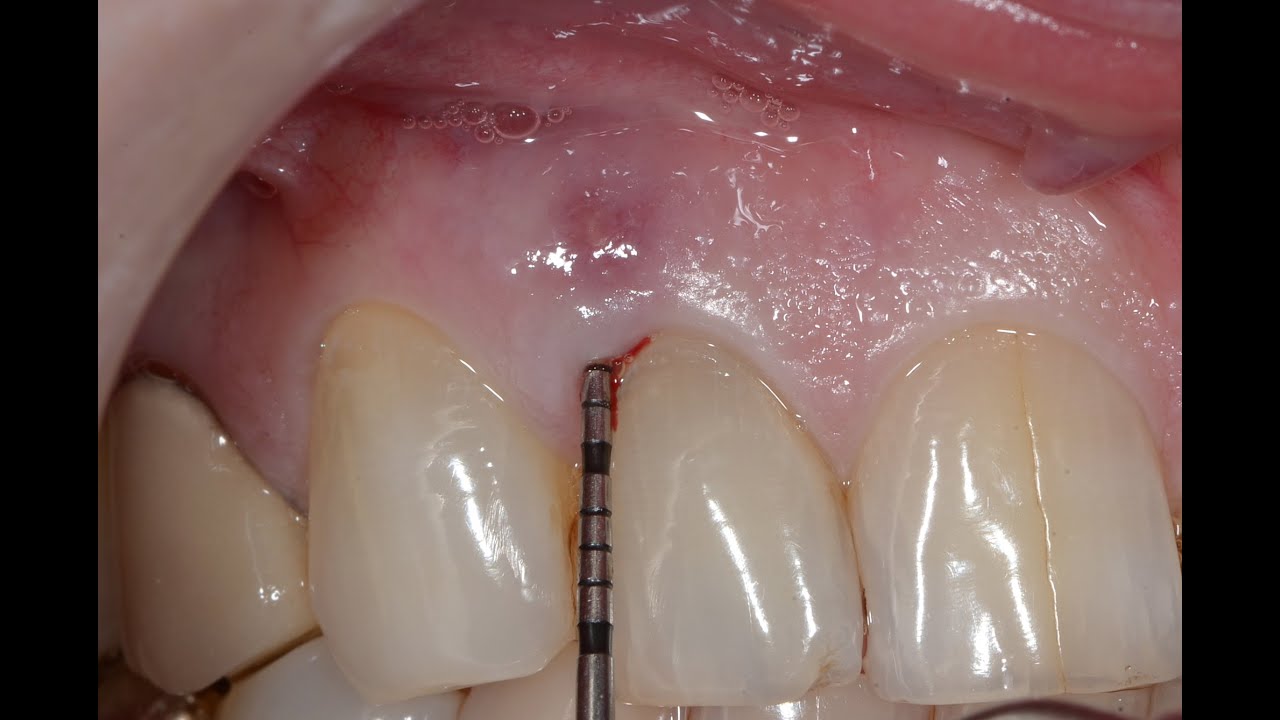

Periodontal Surgery with Regeneration for Lower Teeth YouTube